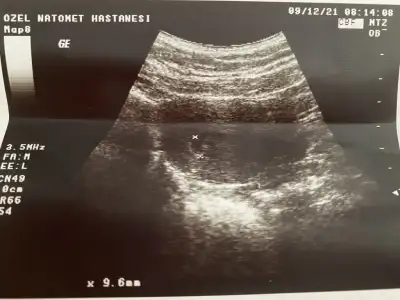

Kızlar keseyi gördüm bugün 🥰

Eklentiler

• BBE0E2A3-DFA1-483C-BB2E-2E21B1277DBA.webp

BBE0E2A3-DFA1-483C-BB2E-2E21B1277DBA.webp

38,8 KB · Görüntüleme: 95